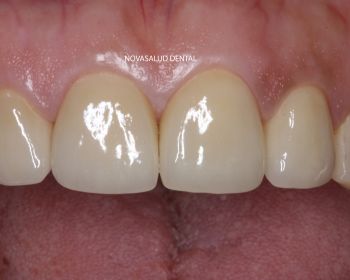

Tratamiento: coronas ceramo-metal unitarias en frente anterior.

Paciente acude a consulta con 4 coronas en sector anterior recién colocadas en otra clínica dental. La paciente no esta nada contenta con el resultado estético. Nos pide que le cambiemos las coronas. Decidimos retirar las 4 piezas ferulizadas y realizar 4 coronas unitarias, es decir, separadas individualmente para ganar en estética. El paciente mejora la estética dental con el tratamiento.